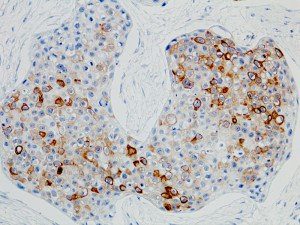

It is the ICU physician who is most likely to witness one of the deadliest manifestations of the abnormal immunological response, the cytokine storm syndrome (CSS). This response is also referred to by some as the cytokine release syndrome (CRS). CSS is characterized by continuous activation and expansion of macrophage and lymphocyte populations, which secrete large amounts of cytokines, causing the cytokine storm. This massive cytokine release is akin to hemophagocytic lymphohistiocytosis (HLH) disease, a syndrome characterized by initial unchecked and persistent activation of cytotoxic T lymphocytes and NK cells.

Clinical and laboratory manifestations of HLH include fever, enlarged liver and/or spleen, neurologic dysfunction, coagulopathy, liver dysfunction, cytopenias (i.e., low levels of erythrocytes, leukocytes, and/or platelets), hypertriglyceridemia, hyperferritinemia, hemophagocytosis, and eventually diminished NK cell activity as the immune system becomes progressively paralyzed. HLH can be familial (primary HLH) or secondary to another disease process (sHLH), such as rheumatic disease, in which it is referred to as macrophage activation syndrome (MAS, characterized by elevated ferritin).